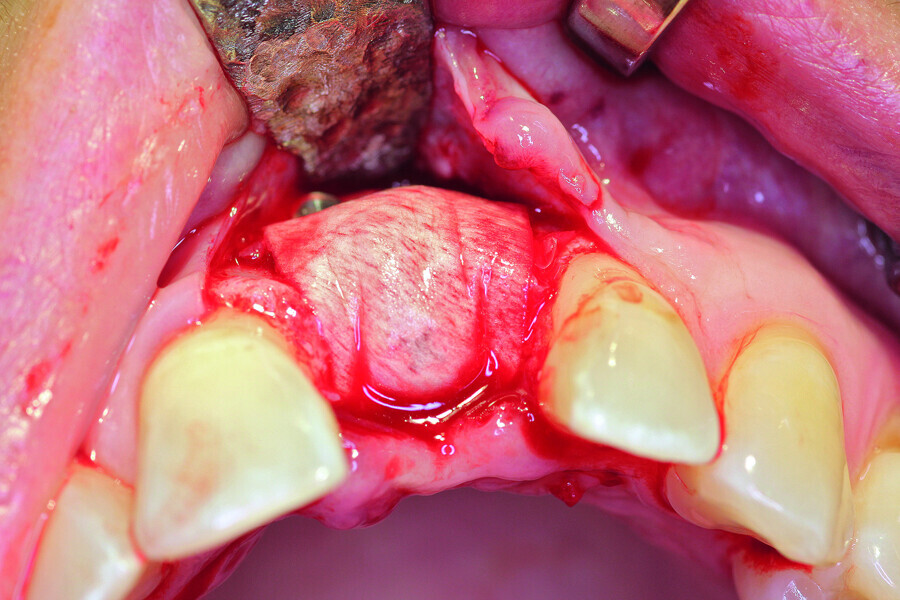

Fig. 6a: Transversal bone augmentation was performed.

Fig. 6b: Transversal bone augmentation was performed.